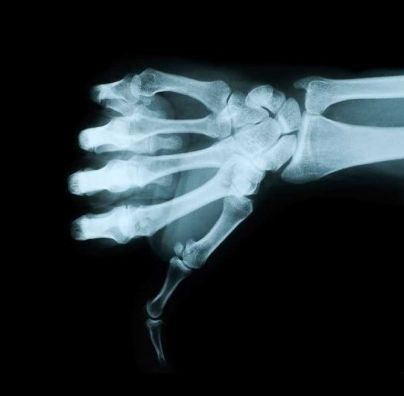

Остеопороз — заболевание, проявляющееся разрежением костной ткани, вследствие чего кости становятся хрупкими и легко ломаются. Именно остеопороз приводит к перелому шейки бедра в пожилом возрасте, который обездвиживает пациента и, в конце концов, приводит к его смерти. Поэтому проблема остеопороза волнует врачей практически всех развитых стран мира.

К сожалению, молоко не только не спасает от остеопороза, но и приносит явный вред. Судите сами. Вы, чтобы защититься от остеопороза, выпиваете по 3 стакана молока в сутки. Белок молока закисляет кровь и выводит кальций из костей. В результате получается, что уровень кальция в крови значительно повышается. Организм, пытаясь нормализовать гомеостаз, начинает складировать кальций туда, куда может. Так появляются кальцинаты в лёгких, почках, головном мозге и костях, мешающие нормальной работе этих органов. Выявить кальцинаты можно при помощи рентгеновского снимка.